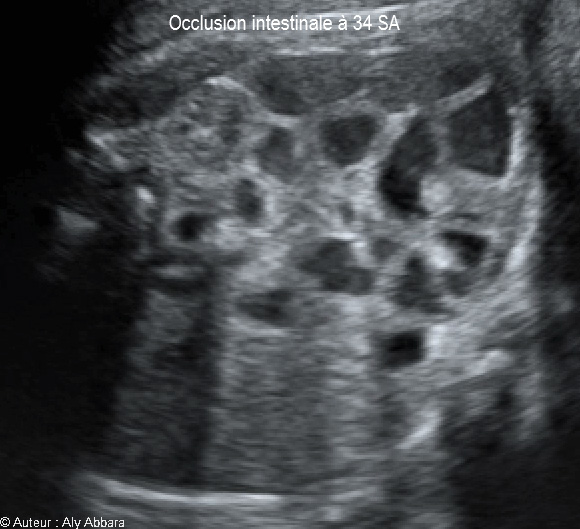

Occlusion intestinale caractérisée par la dilatation des anses grêles et une hyperpéristaltisme : foetus de 34 SA

Images échographiques montrant une occlusion intestinale se manifestant par la dilatation des anses grêles et un hyperpéristaltisme.

Cette occlusion intestinale est liée à la présence, dans la fosse iliaque droite, d'un magma d'anses grêles hyperdenses, agglutinées et obstruées.

L'estomac n'est pas dilaté (occlusion digestive basse), mais on note également l’existence de deux anomalies morphologiques associées :

* Une agénésie du rein droit

* L'absence, au niveau de crosse de l'aorte, de sa 3ème branche, c'est-à-dire l'artère subclavière gauche.

Il s'agit d'une fœtus de 34 SA ; après sa naissance à 38 SA, cette occlusion des anses grêles a nécessité deux interventions chirurgicales digestives dans la période néonatale.